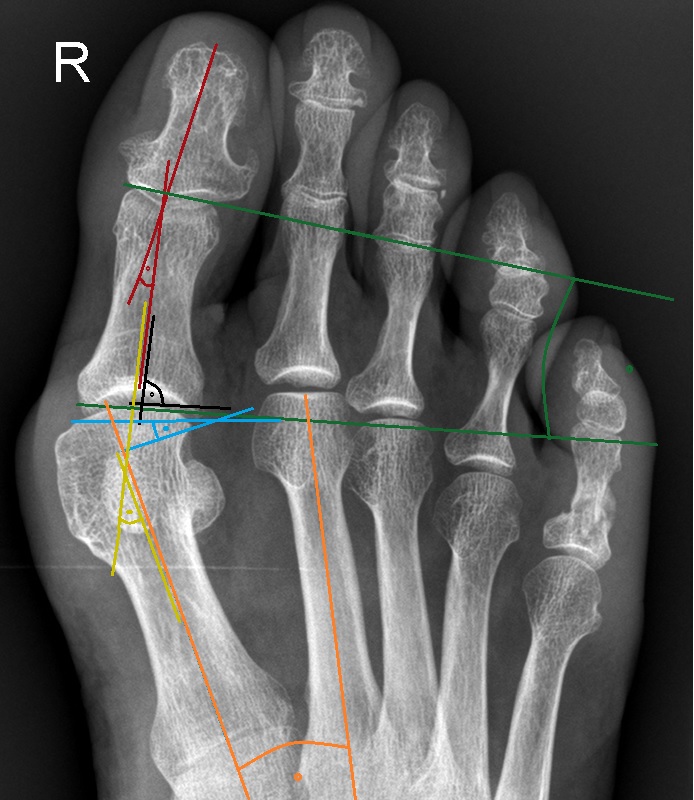

Die Akin-Osteotomie erfolgt in mindestens 50% begleitend zu metatarsalen Osteotomien im Rahmen der Korrektur einer Hallux valgus Deformität 12. Diese gehören zu den am häufigsten durchgeführten orthopädischen Eingriffen. Eine präzise Planung der notwendigen Korrektur unter Berücksichtigung aller Komponenten ist daher unabkömmlich. Dabei sollte eine Valgus-Deformität der Grundphalanx mitbehandelt werden, da diese die Entwicklung eines Rezidivs begünstigt. Die valgische Deformität der Grundphalanx mit veränderten Gelenksflächenwinkeln wird als Hallux valgus interphalangeus bezeichnet (Abb. 1). Dabei können verschiedene Winkel zur Definition der Fehlstellung angegeben werden (Abb. 2) 34. Bei der Beurteilung des Hallux valgus interphalangeus im Rahmen einer Hallux valgus Deformität ist zu beachten, daß häufig eine Hyperpronation der Grundphalanx besteht. Durch diese Malrotation werden die eigentlichen pathoanatomischen Winkel "verprojiziert". Am Röntgenbild erscheinen diese projizierten kleiner als die reellen Winkel. Somit sollte intraoperativ nach einer metatarsalen Osteotomie überprüft werden, ob eine Restfehlstellung im Sinne eines Hallus valgus interphalangeus besteht, da das präoperative Röntgenbild die Fehlstellung nicht immer exakt abbildet.

• Beurteilung des proximalen Gelenkflächenwinkels der Grundphalanx (Proximal Phalangeal Articular Angle, PPAA) des Hallux valgus interphalangeuswinkels (Hallux interphalangeus Angle, HIA) sowie des proximalen zum distalen Gelenksflächenwinkel (Proximal to Distal Phalangeal Articular Angle, PDPAA) 6789 (Abb. 2).

• Bei Hallux valgus Problematik: Bestimmung des ersten Intermetatarsalwinkels (IMA), des Hallux valgus Winkels (HVA), des distalen metatarsalen Gelenskflächenwinkels (DMAA) 68.